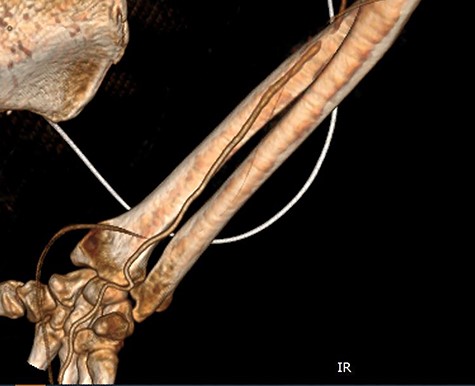

Seven days later, while his general condition was deteriorating, he developed acute ischemia in his right thumb and index finger (Fig. 2). In the ipsilateral forearm, a radial artery catheter had been inserted for monitoring. An urgent radial artery embolectomy was performed and restored the arterial supply to the right hand. The antithrombotic agent was changed to fondaparinux (7.5 mg/once daily). However, within the next few days, it was clinically evident that the revascularization effort was unsuccessful as the thumb and index finger developed dry gangrene. On examination, there was no palpable radial pulse, the ulnar artery pulse was palpable at the level of the wrist and the capillary refill time was normal at the middle, ring and little fingers. A CT angiography (Figs 3 and 4) was performed, demonstrating complete thrombosis of the radial artery beginning at the level of the elbow as well as a 70% occlusion of the ulnar artery ~15 cm proximal to the wrist. Thrombosis of the right axillary vein was also seen (Fig. 5). Orthopedic review was requested for consideration for finger amputation with a recommendation for arm amputation at the level of the elbow. Unfortunately, the patient died 72 h later from respiratory failure following a 24-day admission in ICU.

CT angiography of the right upper limb with volume rendering showing complete radial artery thrombosis beginning at the level of the elbow at the same level that embolectomy was performed. Also, there was significant ulnar artery stenosis near occlusion, ~15 cm proximal to the wrist. The ulnar artery appeared to be normal peripherally to the level of obstruction, with no collaterals being visible.